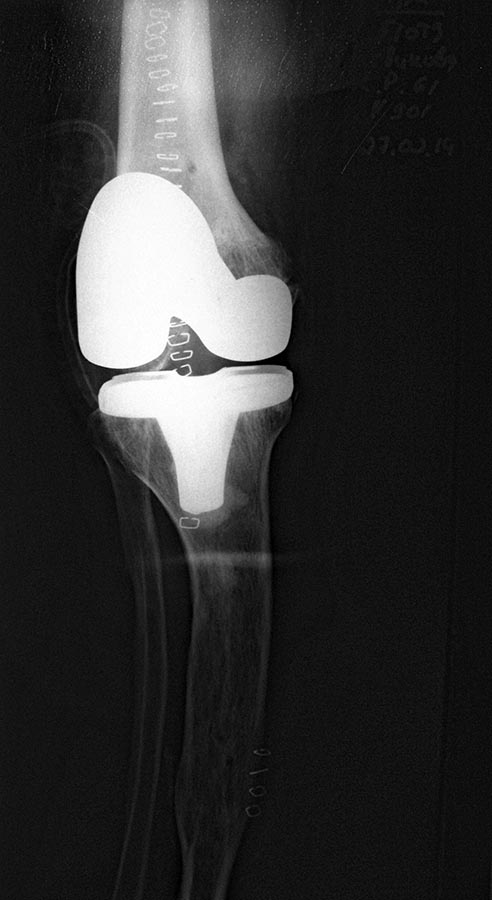

В общем было решено выполнить обычное эндопротезирование. Навигатор нашел точку ротации где-то в позвоночнике, на нее и ориентировались.

Снимки ниже.

Оперировал Проф. Мурылев В.Ю., асс. Рукин Я.А., Середа А.П.

Будем следить. Большое спасибо за советы.